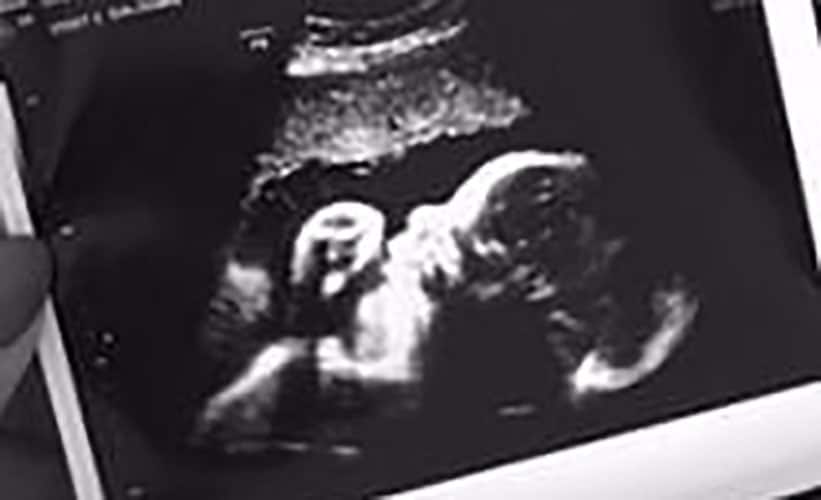

Ultraschallbilder aus dem 2. Trimester (13. bis 28. SSW)

Im 2. Trimester bekommt man oft die schönsten „Ganz-Körper“ Ultraschallbilder. Das Baby ist nun so groß, dass man alles gut erkennen kann und noch nicht zu groß, so dass es noch ganz auf das Bild passt. In dieser Zeit lässt sich meist das Geschlecht bestimmen, wobei manche Babys es einfach nicht preis geben wollen und sich immer so drehen, dass man nichts erkennen kann.